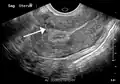

-

A very large (9 cm) fibroid of the uterus which is causing pelvic congestion syndrome as seen on CT -

A very large (9 cm) fibroid of the uterus which is causing pelvic congestion syndrome as seen on ultrasound -

A small uterine fibroid seen within the wall of the myometrium on a cross-sectional ultrasound view -